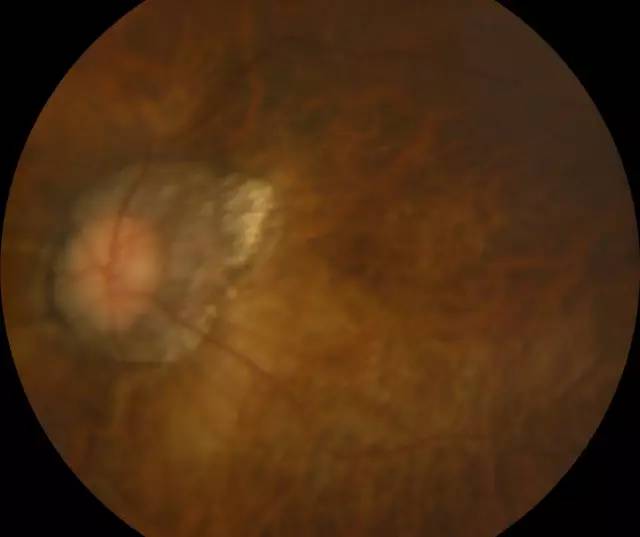

肖先生左眼术前眼底照相图

住院 几天后,赵铁英院长和医护团队给肖先生做了细致的术后检查,肖先生的视网膜已经 正常,左眼也终于能看清东西了。“如果我真的失明了,我觉得整个人生也完蛋了。真的很感谢赵院长,遇到这么好的医生,真的太幸运了!”肖先生不停的表达自己的感激之情。

肖先生左眼术后眼底照相图

赵院长在后来查房时讲到,类似这种超高度近视视网膜脱离的患者,因其视网膜和球壁非常薄弱,玻璃体结构异常,医治起来便非常困难, 率低,且复发率高,所以在选择手术方式时,要充分考虑患者的病情, 衡各种手术方式的利弊。